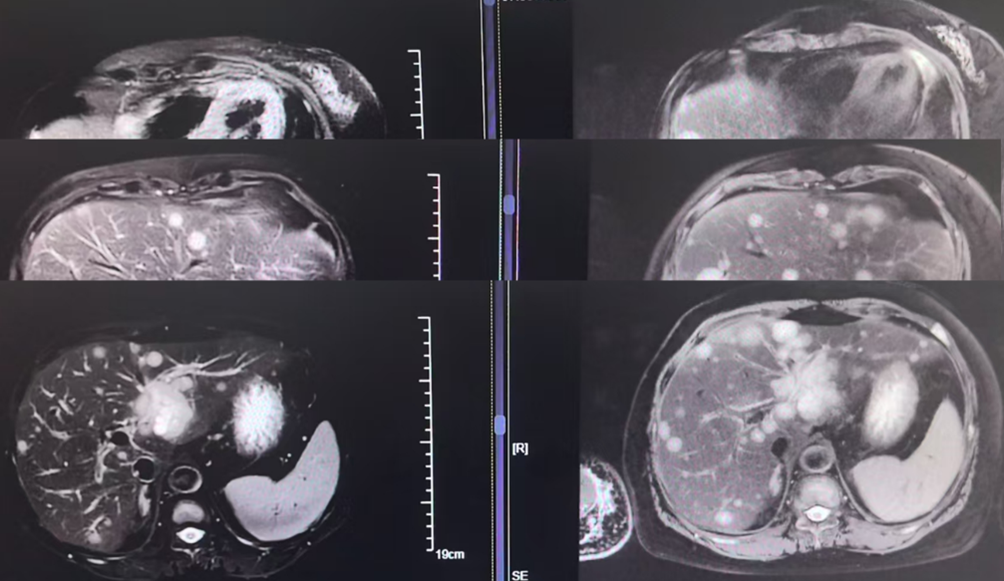

疗效评估: 治疗后复查影像学,患者肝脏病灶显著缩小,评效实现部分缓解。

安全性管理:治疗期间出现骨髓抑制、2级血糖升高及口腔溃疡。团队通过将阿贝西利减量(从150毫克每天2次减至100毫克每天2次)及个体化调整伊那利塞剂量(3至6毫克每天1次),成功平衡了疗效与安全性。患者继续规律治疗至今。

在INAVO120研究中,伊那利塞三联方案将PIK3CA突变人群的中位无进展生存从7.3个月显著延长至17.2个月,降低了58%的疾病进展风险(风险比:0.42)。即便在该例患者已出现脑转移及多脏器转移的高风险负荷下,四线应用含伊那利塞的方案仍能观察到肝脏病灶的部分缓解,这有力证明:针对PIK3CA这一核心驱动基因精准打击,是打破耐药天花板、实现晚期挽救治疗的关键。